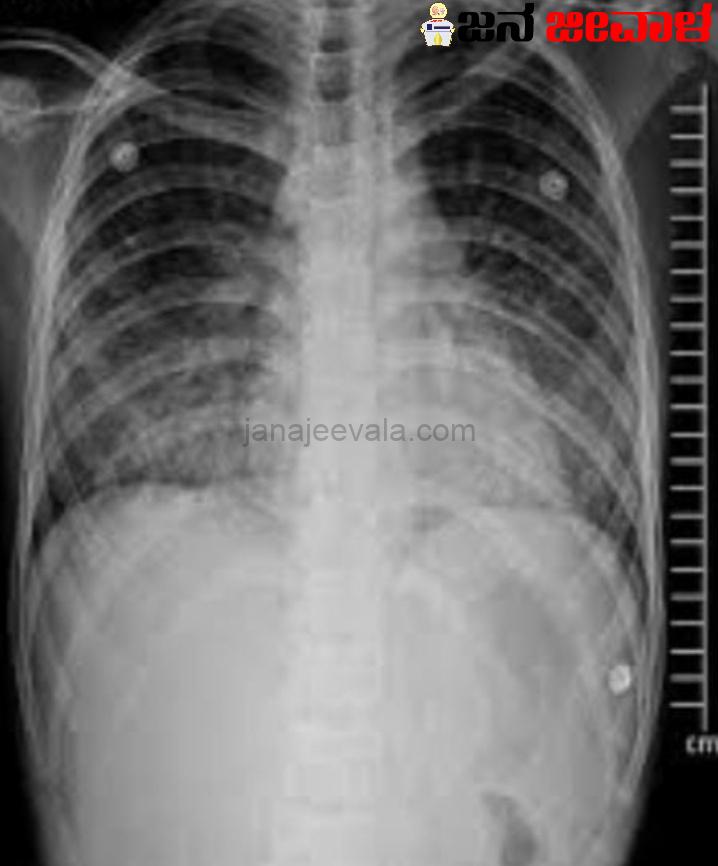

ವೈಟ್ ಲಂಗ್ ಸಿಂಡ್ರೋಮ್ ಎಂಬುದು ನ್ಯುಮೋನಿಯಾದ ತೀವ್ರ ಸ್ವರೂಪವಾಗಿದ್ದು ಅದು ಶ್ವಾಸಕೋಶದಲ್ಲಿ ಗುರುತು ಮತ್ತು ಬಣ್ಣ ಬದಲಾವಣೆ ಉಂಟುಮಾಡಬಹುದು. ಅನಾರೋಗ್ಯದ ನಿಖರವಾದ ಕಾರಣ ಇನ್ನೂ ತಿಳಿದಿಲ್ಲ, ಆದರೆ ಇದು ಬ್ಯಾಕ್ಟೀರಿಯಾ, ವೈರಲ್ ಮತ್ತು ಪರಿಸರ ಅಂಶಗಳ ಸಂಯೋಜನೆಯಿಂದ ಉಂಟಾಗುತ್ತದೆ ಎಂದು ನಂಬಲಾಗಿದೆ.